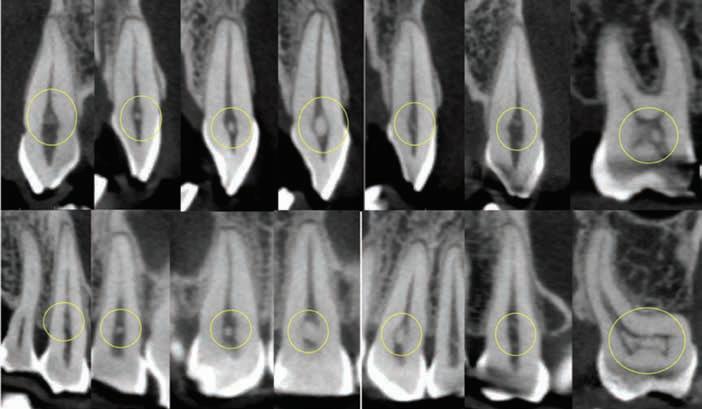

showing distinct pulp stones in canals of teeth #8, 9, 19, 23, 24,

4B. 8X8 CM MORITA ACCUITOMO 170 CONE BEAM CT SCAN—Sagittal and coronal view showing distinct pulp stones in canals of teeth #6, 7, 8, 9, 10, 11, 14. Multiple stones are noticed in the pulp chamber of 14.

Figure 4A. 8X8 CM MORITA ACCUITOMO 170 CONE BEAM CT SCAN—Axial view

25, 26, 27.

Figure

Figure 4C. 8X8 CM MORITA ACCUITOMO 170 CONE BEAM CT SCAN—Sagittal and coronal view showing distinct multiple pulp stones in canals of teeth #19, 22, 23, 24, 25, 26, 30. Single stones noticed in #27, 28, 31.